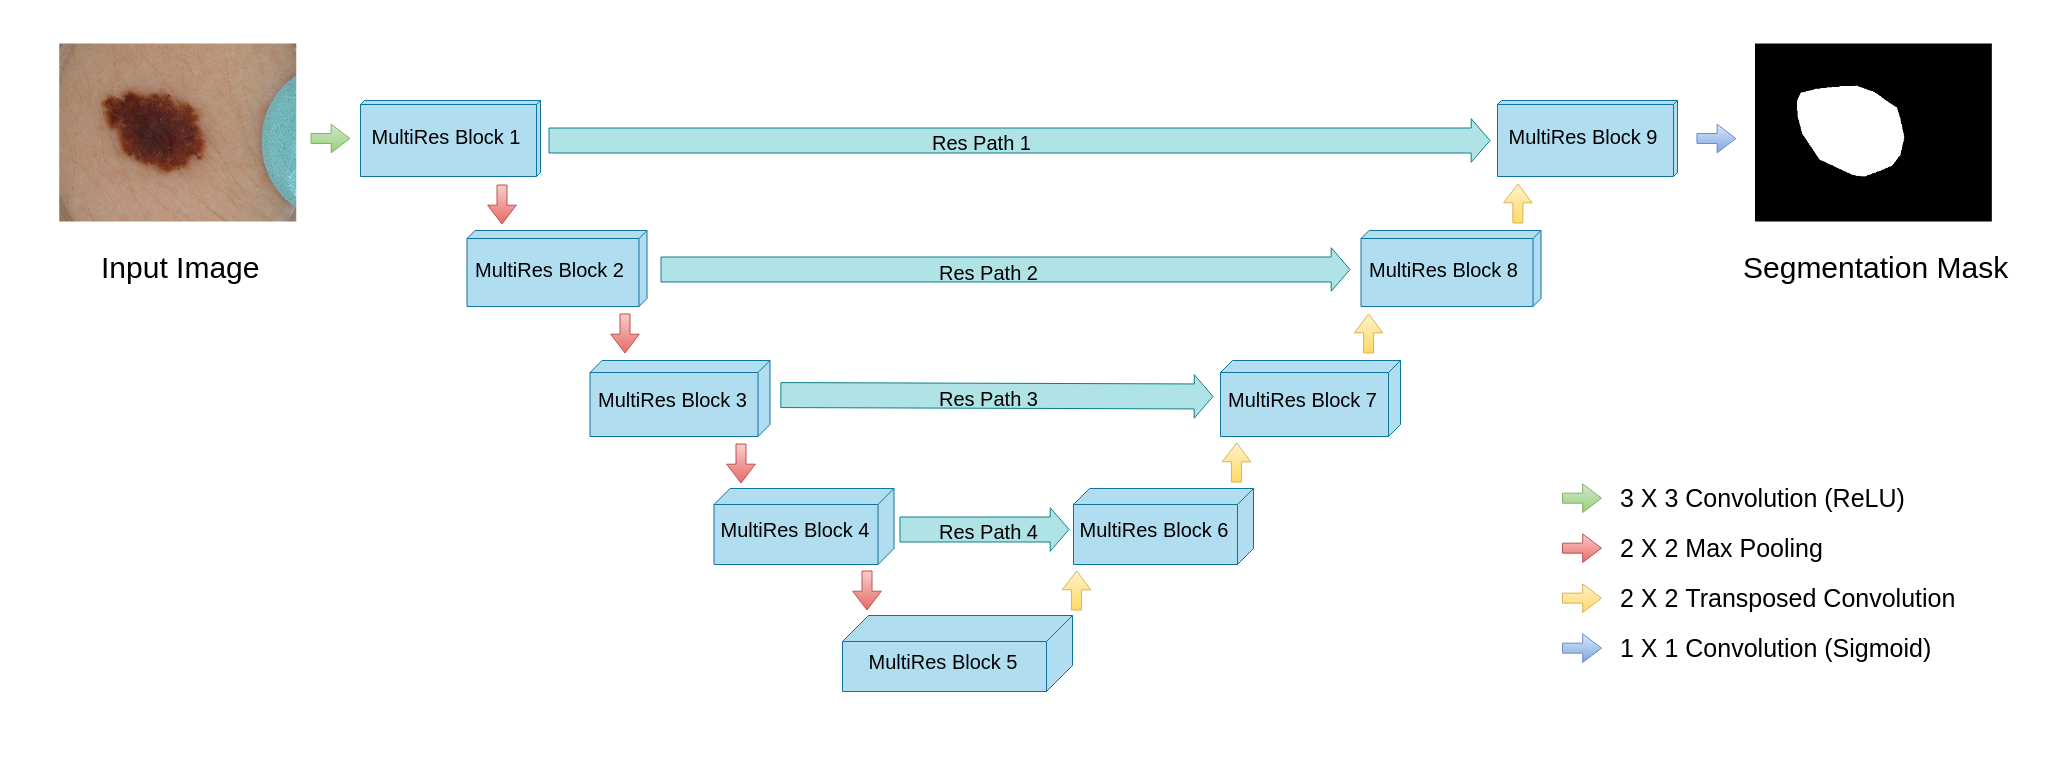

MultiResUNet

The generic design of this network is quite similar to that of U-Net, except for slight differences in the nature of convolutions in each layer and the residual path from the encoders to the decoders (Figure 2). Each layer of U-Net is replaced by a MultiRes block that contains 4 convolutions (Figure 2(b)). The skip connections of U-Net are replaced by Res Paths (Figure 2(c)) as described in [25]. The motivation of adopting this network comes from the idea that an ideal architecture should be able to assess images having diversified scales in medical image segmentation procedures. For further details readers are referred to [25].

(a) Network architecture

(b) MultiRes block

(c) Res Path Figure 2: MultiResUNet architecture. Figure borrowed from [25]. -